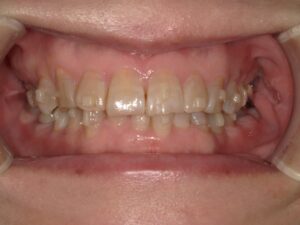

初診時54歳女性 体に不調を感じるとのことでした。夜間熟睡ができない。若い時は肩こりや頭痛もあった。左でよく噛んでいる。ということでした。口腔内を拝見すると下の前歯の真ん中が少し左にずれていました。かみ合わせた時に下の前歯は上の前歯に少し覆われるのが一般的なのですが、半分以上隠れています。歯科用語では過蓋咬合と言います。かみ合わせた時に下の前歯が上の前歯で完全に覆われている方もいらっしゃいます。下の前歯の付け根当たり、犬歯がわかりやすいかもしれません。骨がもっこりしているように見えます。かみ合わせが強い方によく見られます。骨隆起と言います。上の真ん中から3番目の犬歯が一つ後ろの歯に比べて内側に傾斜しています。

かみ合わせの高さが低くなるにつれ、噛む筋肉は強く作用する。

前歯のてっぺんがすり減っているのもわかると思います。本来犬歯は山のように先端が少し尖っているのですが、平らになっています。これは噛みしめてすり減っているか、歯ぎしりしていることが考えられます。たいていの方はそんなことはない、家族にも言われたことがない、など強く否定されます。でも痕跡はあります。では何故噛みしめるのでしょうか。顎は上顎が先に大きくなり、そのあとから下顎が大きくなるという成長過程をとります。上顎が適正に大きくならないと、後から成長する下顎が前への成長がブロックされます。上の前歯に下の前歯が当たってしまうと下顎は後ろに下がります。下がると気道が狭くなり、苦しいので本能的に前に出そうとします。また奥に下顎が下がるとかみ合わせの高さが低くなってしまいます。かみ合わせが低くなると筋肉は強く作用します。成長期に適正に顎が大きくなれず、その時期を過ぎて不正咬合のままであることが気道を狭くしたり、噛む筋肉を強く作用させてしまうことが噛みしめや歯ぎしりの理由ではないかと考えています。エラの張りもかみ合わせの高さが低くなって筋肉が過緊張を繰り返し、変な言い方ですが鍛えられていった結果で起こります。噛み合わせの低い方に噛み癖があります。顔の傾きや顎にズレが出ます。加齢によるすり減りだけでは根拠が薄いのです。